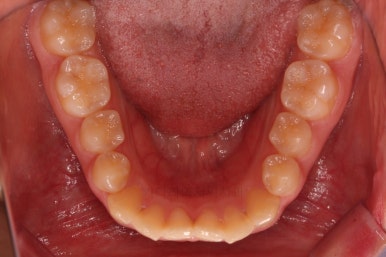

치열이 매우 바르게 되었고 교합도 양호하며 뻗쳐 있던 앞니 각도도 좋아졌네요.

돌출의 느낌도 처음보다 많이 좋아졌어요.

웃을 때 보이는 치열의 느낌도 좋고요.

전후 사진을 비교해 볼게요.

입술의 두께로 인한 돌출감 개선에 약간은 한계가 있었지만 그래도 본인이 만족한 수준에서는 돌출감을 개선했고 치열도 매우 가지런하게 마무리를 할 수 있었답니다.